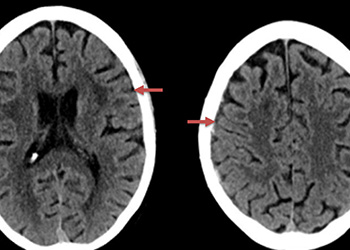

Figure 1: A) Non Contrast CT and B) MRI FLAIR studies demonstrate subtle Subarachnoid hemorrhage in the sylvian and parietal sulci (arrows) The subararachnoid hemorrhage was […]

Figure 1. A) 6 weeks post mild trauma B) 4 weeks post mild trauma demonstrate stable subacute subdural collections with mild growth and sulcal effacement. The […]